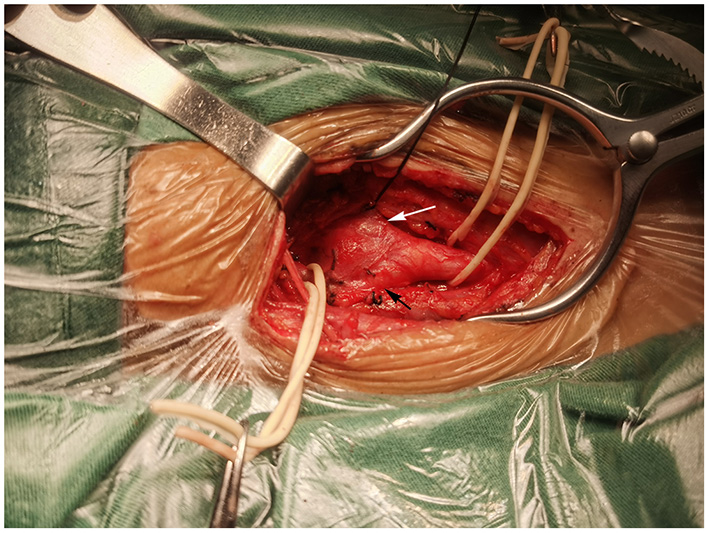

Surgery was performed in a supine position under general orotracheal anesthesia, and the neck was slightly hyperextended and rotated to the left. A longitudinal incision along the anterior border of the right sternocleidomastoid muscle was made to expose the carotid bifurcation and the tumor (Figure 2). Proximal and distal arterial control was obtained by exposing the common carotid artery, internal carotid artery, and external carotid artery cephalad to the mass. Then, the tumor was gradually separated from the carotid arteries in cranial to caudal direction along the subadventitial plane using bipolar electrocautery. Cardiac arrest suddenly occurred when dissecting the tumor from the carotid bifurcation. The systolic blood pressure (sBP) dropped from 115 to 40 mmHg. This complication was managed immediately with external cardiac massage and administration of a single intravenous 0.5-mg atropine dose while simultaneously suspending CBT manipulation. The cardiac activity recovered ~40 s after asystole. The heart rate and sBP returned to 72–80 bpm and 120 mmHg, respectively. The manipulation was then completed while gently assisted by topical anesthesia with 2% lidocaine. The patient was closely monitored after surgery and a decrease in the heart rate and blood pressure level was not noted. On the second day after surgery, the patient complained of left chest pain during exercise. Chest X-ray showed no rib fracture, and reexamination of the electrocardiogram indicated normal results. The level of myocardial enzymes was not elevated. The pain was relieved over time without analgesia treatment. The patient had no neurological sequelae or cranial nerve injuries after surgery and was discharged 1 week after surgery. Histopathological examination revealed a zellballen pattern characteristic of paraganglioma and did not show any evidence of malignancy (Figure 3A). Immunohistochemical results were positive for synaptophysin, chromogranin A, and CD56 in the tumor cells and S-100 protein was present in the sustentacular cells (Figures 3B–E). Both synaptophysin and chromogranin A are neuroendocrine markers located in neuroendocrine granules. CD56, known as a neuronal cell adhesion molecule, is a membrane glycoprotein present on the neural cell surface. These positive immunohistochemical stain profiles supported the diagnosis of CBT. The patient had no complaints at 1-month follow-up after surgery.

Figure 2

Intraoperation view of right carotid body tumor resection. A mass at the bifurcation splayed the internal carotid artery (black arrow) and external carotid artery (white arrow).